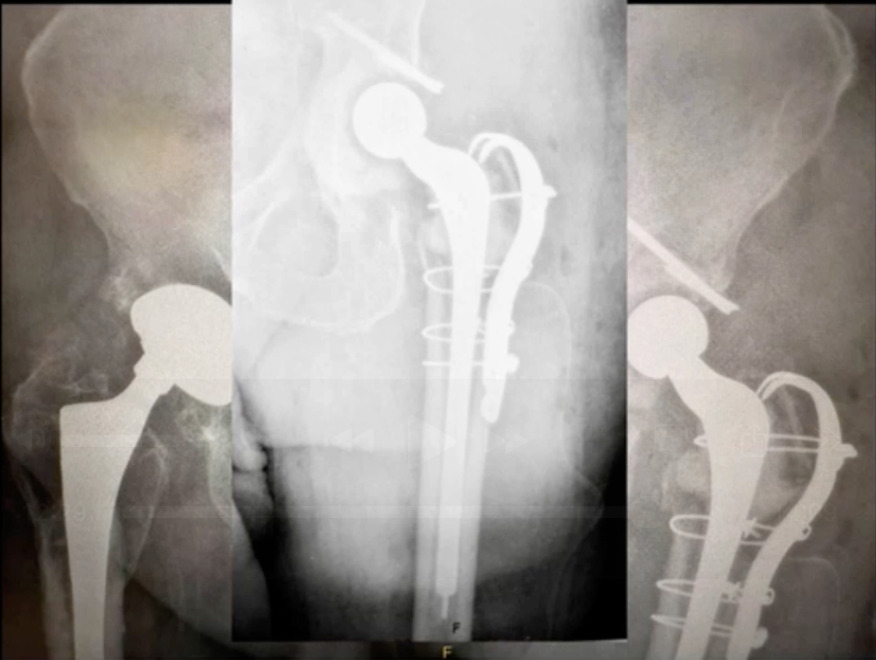

Also, I definitely like to avoid multiple implant representatives and companies, and in the OR, I like to stick with one. One of the problems I see is that there’s just so many people in the operating room. I have to “get 'em out of the way.” Actually, I can even operate on people. That’s important. That would be number six. Just to show you a case example this was a male patient came in with bilateral hip pain. (Figure 5)

His hips were done quite a while ago and recently, he had a coronary artery bypass. He’s got melanoma venous insufficiency. Just very exciting history. He’s pretty much a B bordering, not a C patient, but a definitely a B patient. We aspirated his right hip. It was negative, but the left hip unfortunately was positive on aspiration. He came back polymicrobial on next generation sequencing. But the only bug we came up with on culture was a corynebacterium. He had asymmetrical poly wear. We also did a metal ion workup through blood testing and he had really high metal ion levels. I was really concerned that he had worn through in an area and had metal ion activity. To look at it face value you’re prone to say, “okay, we can do that.” But things don’t always work out well.